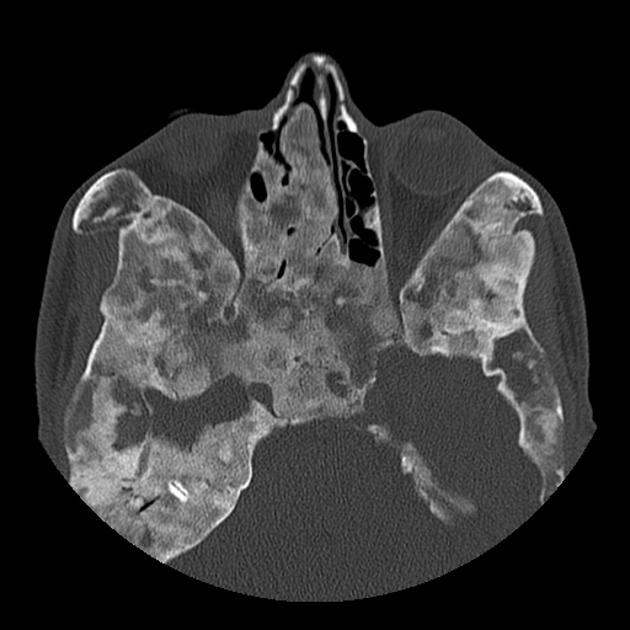

Fibrous Dysplasia

Syndromes:

McCune Albright (polyostotic fibrous dysplasia, precocious puberty and cafe au lait spots)

Mazabraud (fibrous dysplasia and soft tissue myxomas)